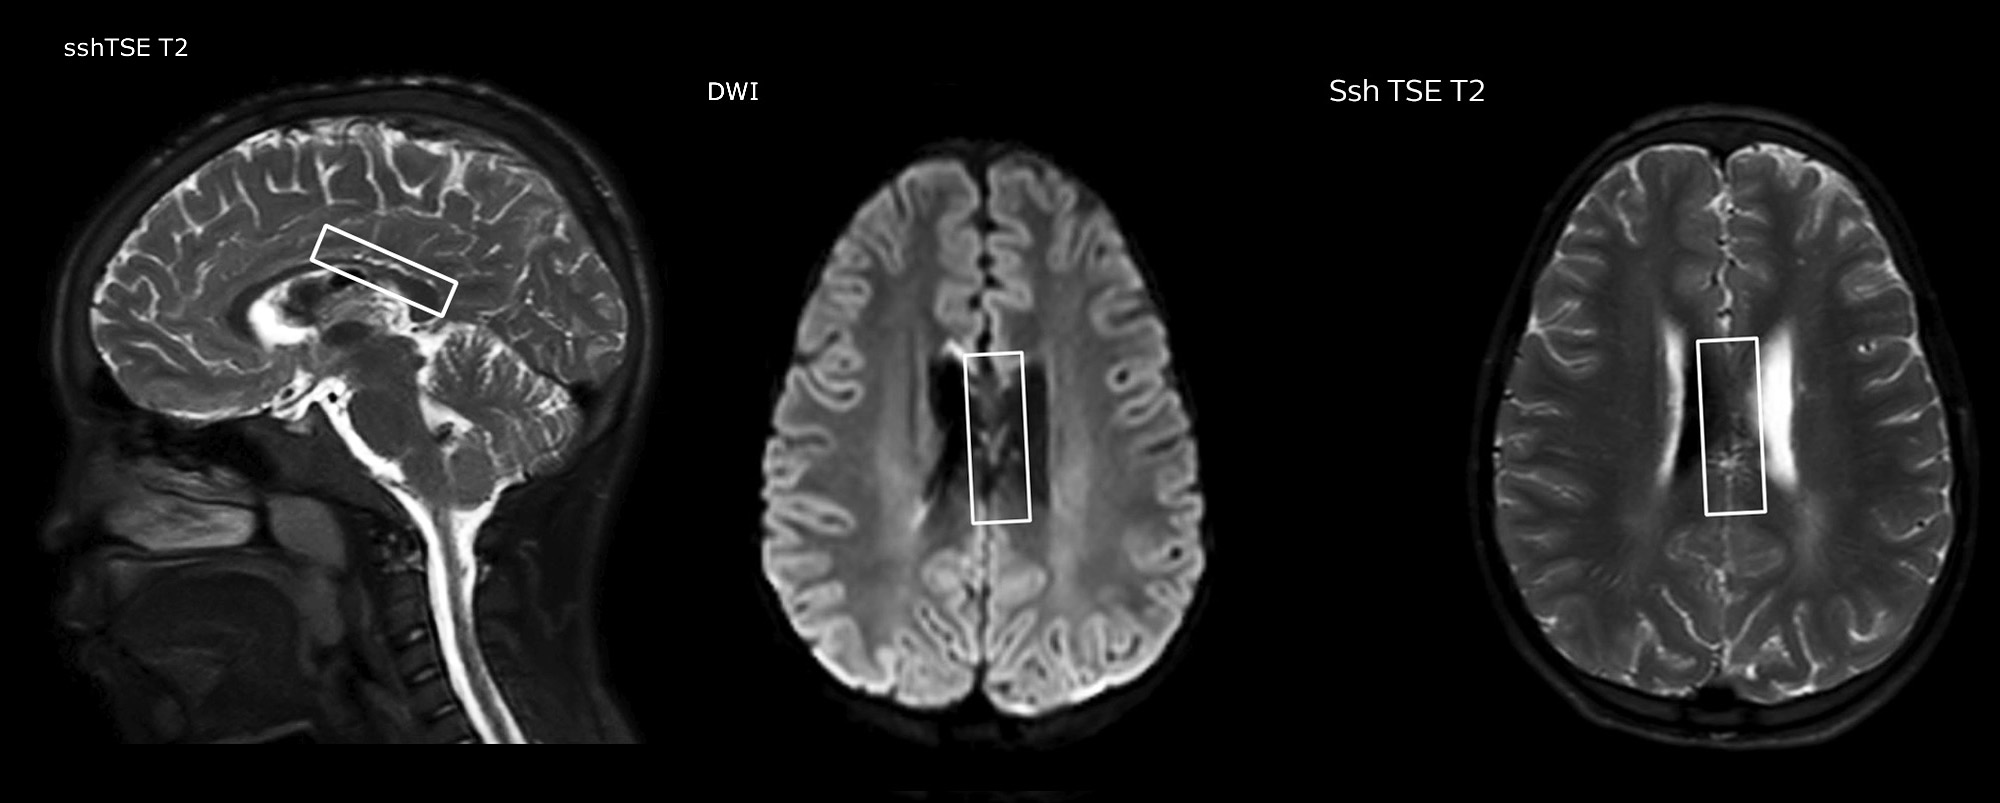

Pseudo-continuous arterial spin labeling (pCASL) was developed for brain perfusion imaging without contrast agent. “This is very desirable in pediatric patients where the general trend is to limit the administration of contrast,” says Dr. Miller. Growing confidence in specific applications “We built up confidence in pCASL by comparing it to contrast-based perfusion imaging. Once we had confidence that it was representing what the contrast perfusions were representing, we increased our diagnostic confidence by serial imaging in either the acute stage or the long term stages in a number of patients with arterial abnormalities.

Dr. Miller uses pCASL for all patients who present with chronic and acute cerebrovascular abnormalities such as acute stroke, as well as patients who present with signs of acute inflammation in the brain, and occasionally in patients with tumors, to assess the perfusion status of their tumor.

“In combination with diffusion weighted imaging, it can help give a more extended assessment of the degree of perfusion abnormality in a patient who is suffering acute ischemia. We have a number of patients who have chronic arterial insufficiency due to prior arterial abnormalities or acquired arterial abnormalities such as sickle cell disease or neurofibromatosis. Sometimes the child’s first manifestation of disease progression is a reduction in brain perfusion before stroke symptoms manifest clinically or in diffusion weighted imaging. We use pCASL to help delineate the perfusion abnormality.”

To other new users I would recommend to also start to interpret the pCASL images in comparison with other standard imaging – T2 and FLAIR and DWI – until the user gains confidence in interpreting these images by themselves.” “A powerful use of pCASL is in patients with chronic cerebrovascular stenosis, where clinicians desire information on how compensatory mechanisms of the brain are performing to enable perfusion to the brain. Often clinicians take into account how the compensatory mechanisms appear to help to provide adequate perfusion to the patient’s brain, and they may intervene surgically or make some other management decision.” “Another special application is the assessment of cerebrovascular reactivity with a Diamox perfusion exam, where we subtract two sets of pCASL images.”